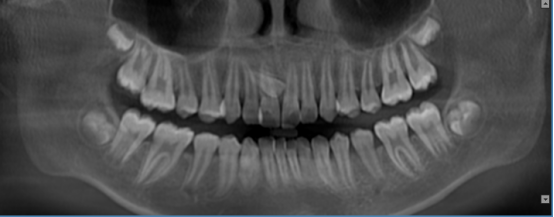

正畸通过扫描形成图像,包括曲面体层、头颅侧位进行测量图像。2D和3D图像在确定多生牙的存在及位置方面,有着巨大的差别。3D图像对扫描区域有着完整,综合的展示,甚至允许通过不同视角,以及对不同断面重建图像进行观察。